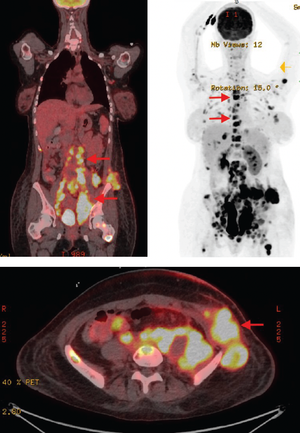

A young woman presents with painless lumps to the emergency department and is later diagnosed with clear cell carcinoma.